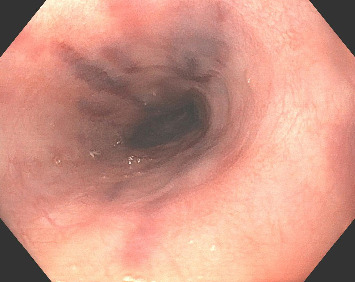

Abstract Image

Kaposi sarcoma (KS), an angioproliferative neoplasm driven by human herpesvirus 8, predominantly affects patients with acquired immune deficiency syndrome (AIDS) or those on immunosuppressive therapy. Gastrointestinal involvement in KS is underreported, with limited literature highlighting its clinical significance and morphological diversity on endoscopy. This case report illustrates the complexities of diagnosing and managing gastrointestinal KS in an AIDS patient who presented with upper gastrointestinal bleeding. The diagnosis was established through the characteristic endoscopic appearance of the lesions, supported by histopathological confirmation. This case emphasizes the variable endoscopic manifestations of KS, ranging from linear ulcers to nodular lesions, and underscores the necessity for heightened clinical vigilance and multiple deep biopsies to avoid false-negative results. Treatment options, primarily palliative, include highly active antiretroviral therapy, chemotherapy, and radiation, yet the prognosis remains poor with high short-term mortality. This report contributes to the sparse literature on gastrointestinal KS, advocating for increased awareness and early intervention to potentially improve outcomes in this patient population.